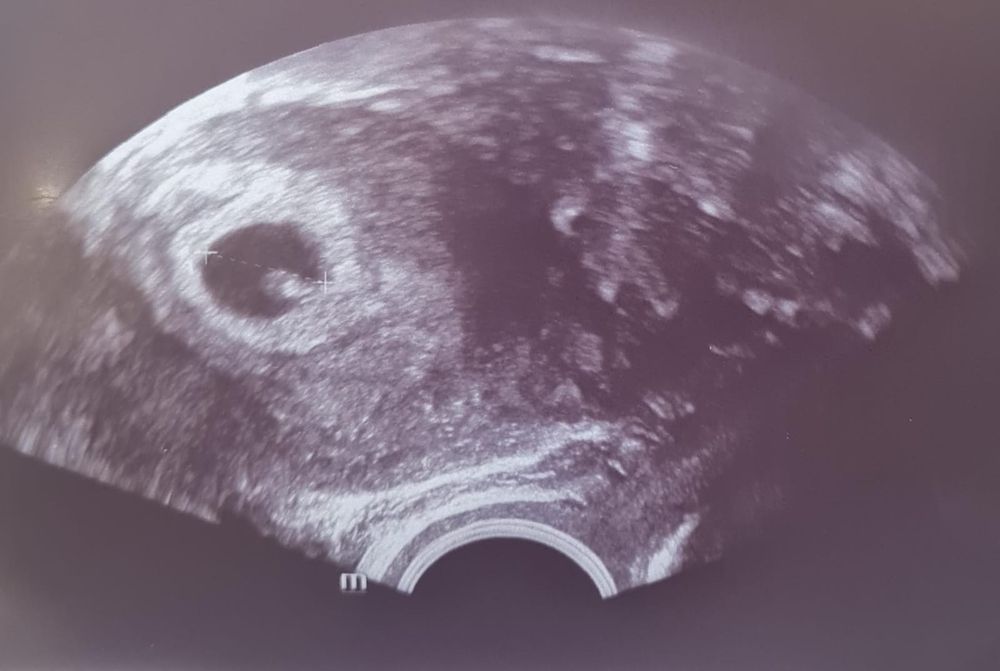

5-ый крио (ЕЦ) - 26 дпп - УЗИ